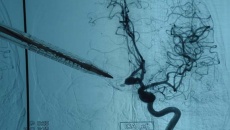

Phình động mạch được chẩn đoán tại bệnh viện bằng các xét nghiệm hình ảnh chuyên biệt như chụp cộng hưởng từ mạch máu (MRA), chụp cắt lớp vi tính mạch máu (CTA) hoặc chụp mạch số hóa xóa nền, giúp bác sĩ có được hình ảnh chi tiết về não và mạch máu.